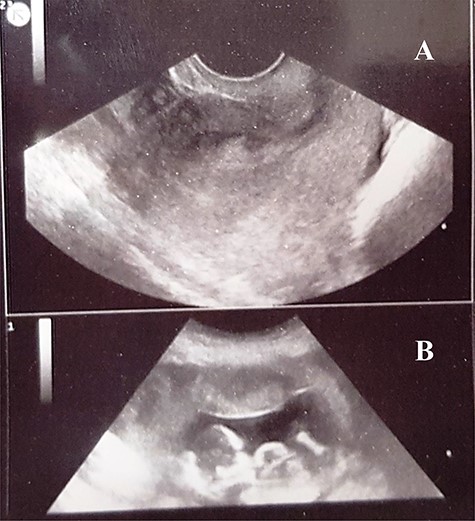

On examination, she was pale, ill-looking, hemodynamically unstable and temperature 36.8°C. There was mild abdominal distention, left iliac fossa and supra-pubic tenderness and guarding. On speculum examination, there was a single closed cervix with mild bleeding from its external os. Digital vaginal examination showed mild cervical motion tenderness, all fornices were fulled, the uterus was slightly enlarged and there was a tender left adnexal mass. An urgent 2D pelvic ultrasound scan revealed a slightly enlarged uterus (12 x 9 x 8 cm), with an emptied uterine cavity and a thick endometrium. Adjacent to the uterus, a gestational sac of ~7 x 6 cm containing a fetus corresponding to 11 weeks of pregnancy (Fig. 1). The fetus had no cardiac activity. The scan also showed free fluid in the Morrison’s pouch, the pelvis and abdomen estimated at 1300 mL. The diagnosis of a ruptured ectopic pregnancy was made. A pre-operative workup result is illustrated in Table 1.

A 2D pelvic ultrasound scan showing a normal size uterus, with thick endometrium (A), peritoneal fluid, and an abdominally aborted gestational sac containing a dead embryo (B) mimicking a ruptured ectopic pregnancy.